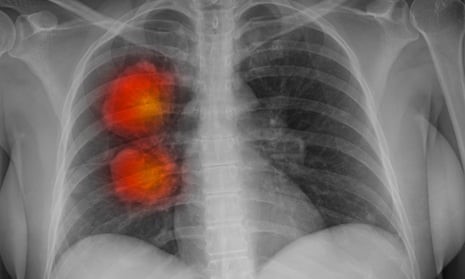

Ung thư phổi là nguyên nhân gây tử vong do ung thư lớn nhất trên toàn thế giới.

Ung thư phổi là nguyên nhân gây tử vong do ung thư lớn nhất trên toàn thế giới và chiếm 1/5 (21%) số ca tử vong do ung thư ở Anh, song dữ liệu gần đây cho thấy hơn 60% bệnh ung thư phổi ở nước này được chẩn đoán ở giai đoạn 3 hoặc 4. Lee cho biết những người được chẩn đoán ung thư phổi ở giai đoạn sớm nhất có khả năng sống sót qua 5 năm cao hơn so với những người được phát hiện muộn, do đó, ưu tiên hàng đầu của nhóm nghiên cứu là tìm cách tăng tốc độ phát hiện bệnh và có thể hỗ trợ các bác sĩ xác định sớm những bệnh nhân có nguy cơ cao.